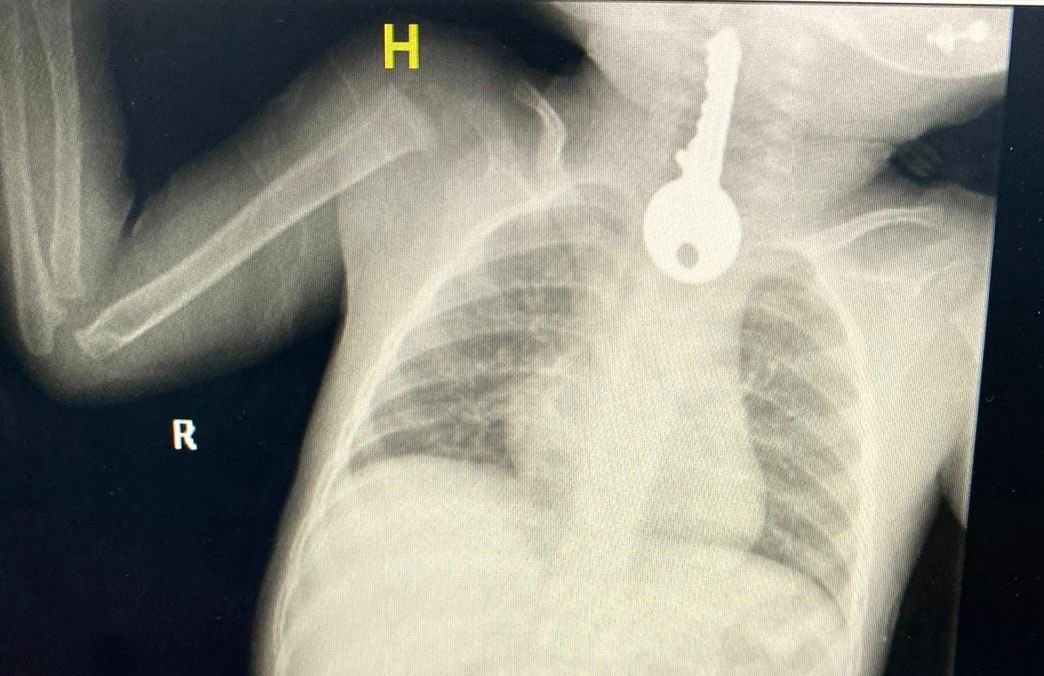

وأوضح مجمع الملك فيصل الطبي عبر حسابه في "تويتر"، أنه استقبل حالة طفل في وضع صحي حرج يعاني من ضيق في التنفس مما استدعى تقديم الإسعافات الأولية وإجراء الفحوصات السريرية والإشعاعية التي كشفت وجود جسم غريب على شكل مفتاح في المريء.

وقال الفريق المعالج للحالة إنه تم على الفور عمل منظار عاجل واستخراج مفتاح حديدي من المريء كاد أن يودي بحياته ثم متابعته في قسم التنويم من قبل الفرق التمريضية حتى استقرت الحالة وخرج بالسلامة ولله الحمد.